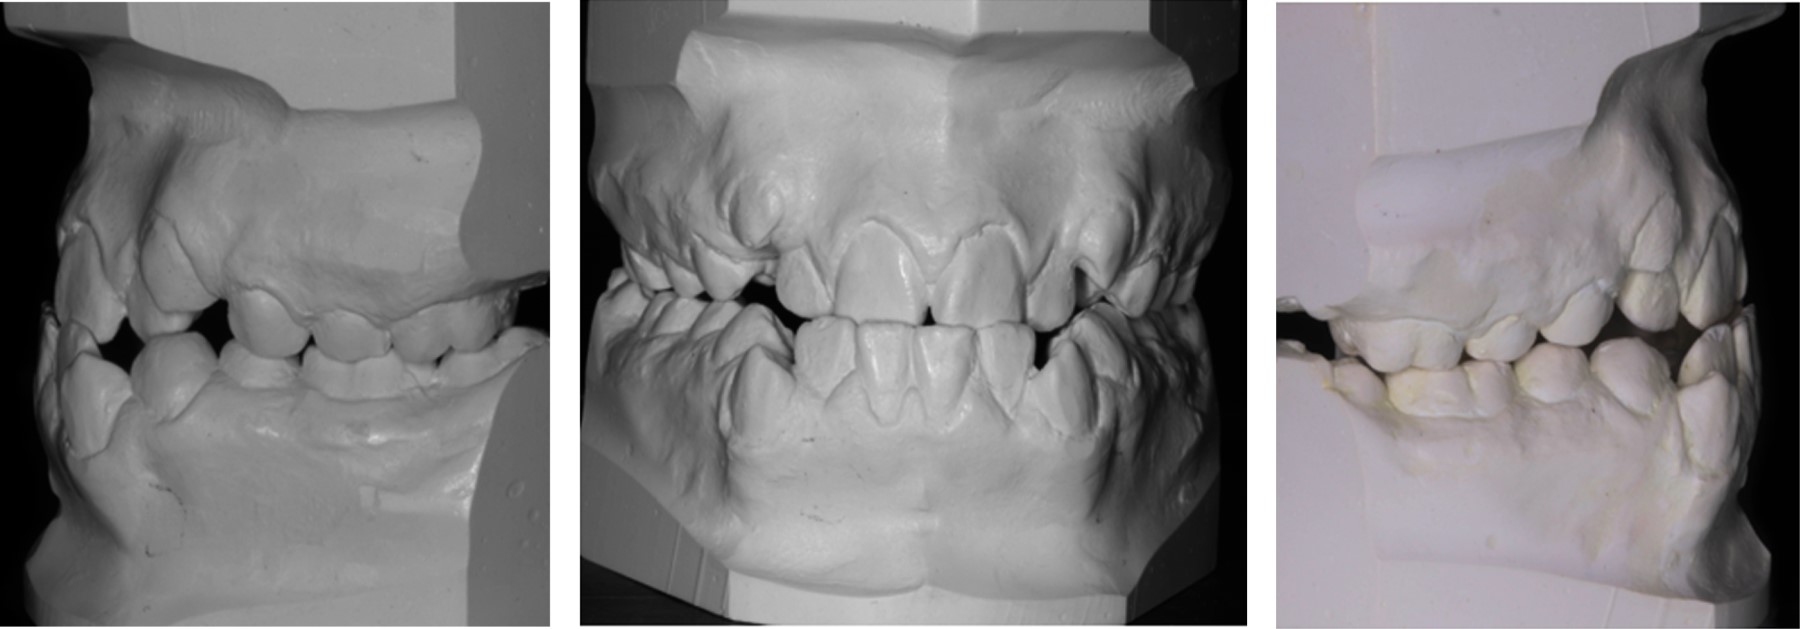

Análisis de modelos

El análisis de Bolton presenta un exceso mandibular de 6-6: 3.5 mm y un exceso mandibular de 3-3: 3 mm. Presenta una discrepancia de longitud de arco superior de -10.3 mm e inferior de -7 mm (Figura 2).

Figura 2